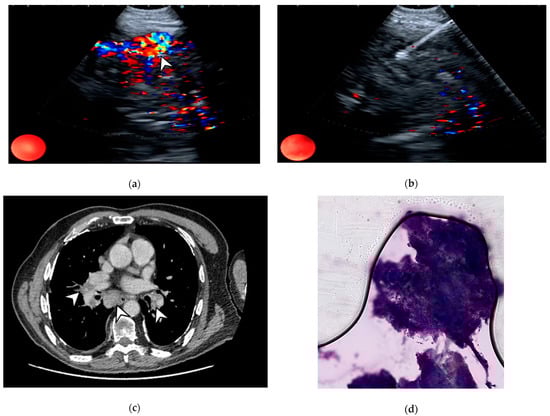

- Nakajima, T.; Anayama, T.; Shingyoji, M.; Kimura, H.; Yoshino, I.; Yasufuku, K. Vascular Image Patterns of Lymph Nodes for the Prediction of Metastatic Disease During EBUS-TBNA for Mediastinal Staging of Lung Cancer. J. Thorac. Oncol. 2012, 7, 1009–1014. [Google Scholar] [CrossRef] [PubMed]

- Nosotti, M.; Palleschi, A.; Tosi, D.; Mendogni, P.; Righi, I.; Carrinola, R.; Rosso, L. Color-Doppler Sonography Patterns in Endobronchial Ultrasound-Guided Transbronchial Needle Aspiration of Mediastinal Lymph-Nodes. J. Thorac. Dis. 2017, 9, S376–S380. [Google Scholar] [CrossRef] [PubMed][Green Version]